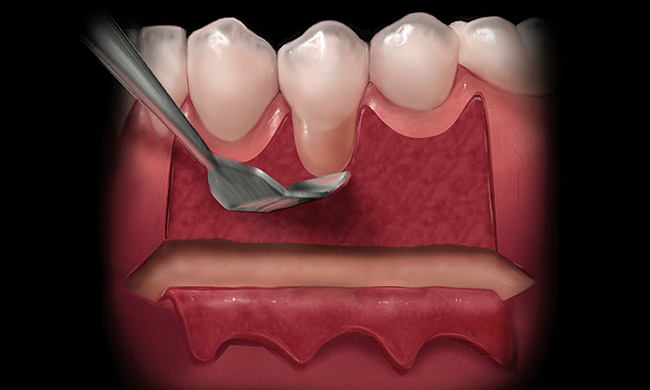

A periosteal elevator should be introduced into the first incision and the connective tissue elevated to remove the tissue between the epithelium and palatal bone. The wedge of tissue is removed by grasping the band of epithelial tissue and teasing out the attached connective tissue. Wet gauze should be placed over the donor site and firm pressure exerted for 5 minutes to prevent hematoma formation under the epithelial tissue. The incision should then be closed with resorbable sutures in a crisscross-style horizontal mattress suture.3 Patient comfort may be increased by use of a vacuform stent worn for the first 2 weeks after harvesting of the palatal graft.4

Figure 5  A periosteal elevator is used to create a full thickness elevation apical to the mucogingival junction.

Figure 5